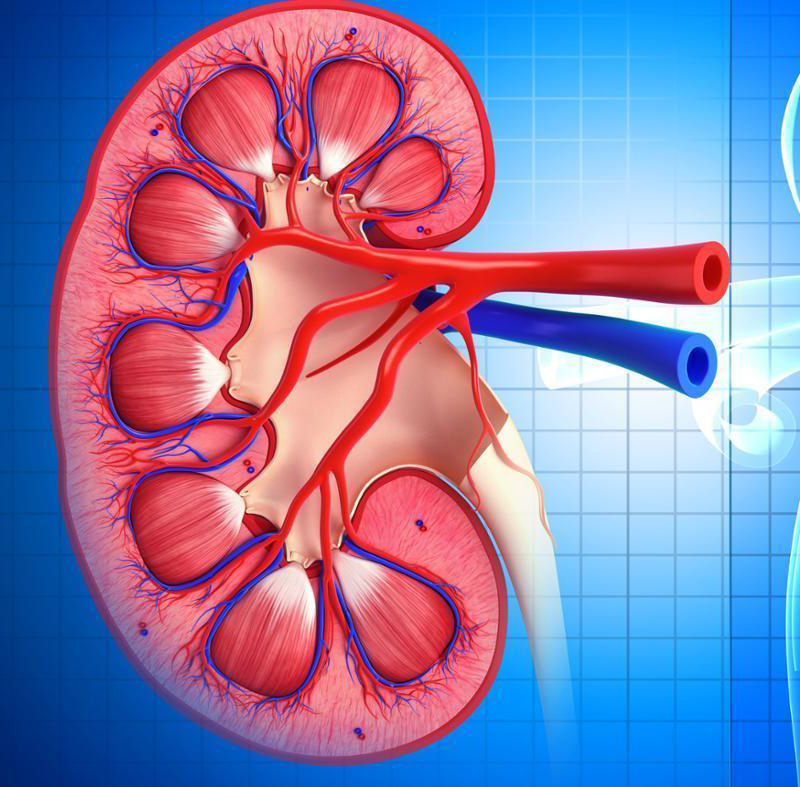

Симптомы подострого гломерулонефрита: фото и описание

Раздел: Визуальный дайджест